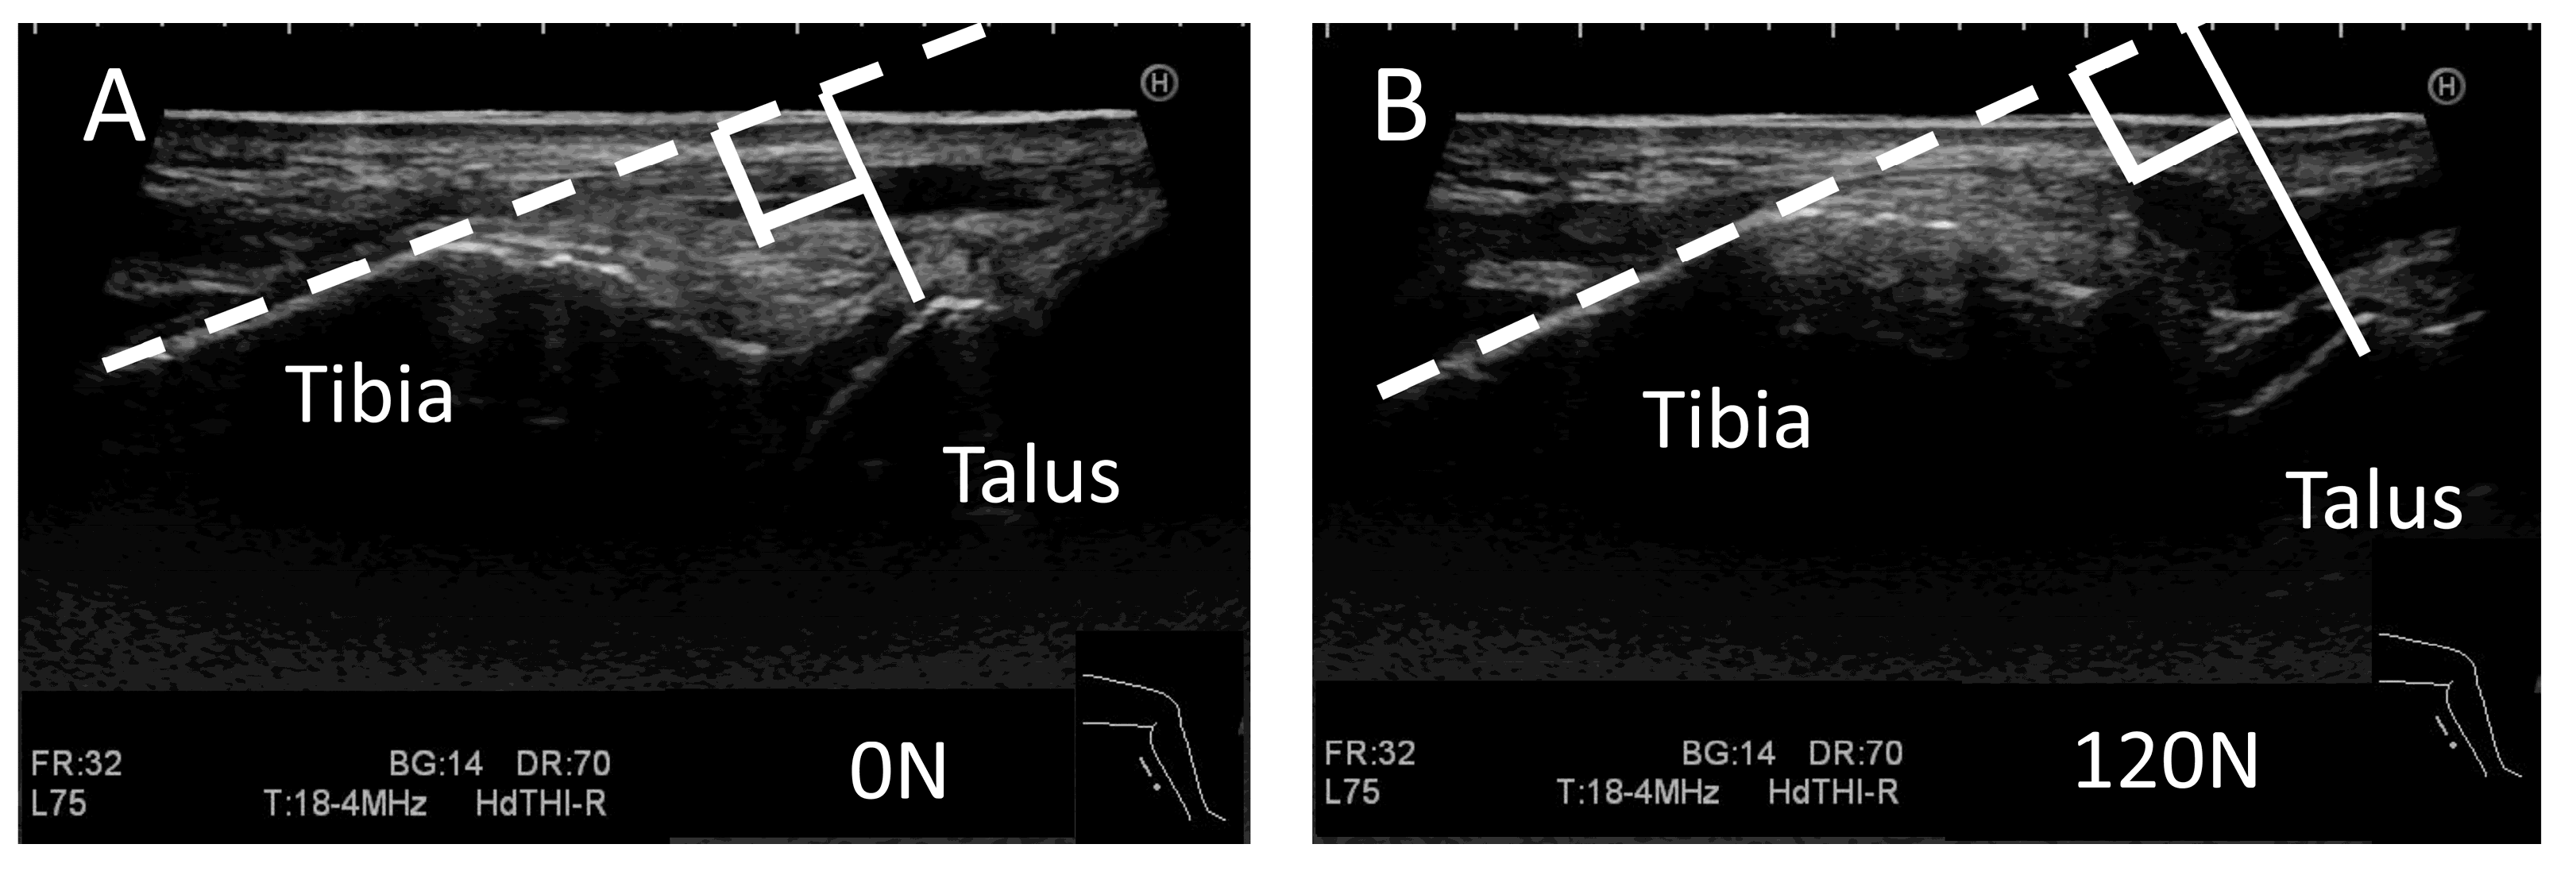

2.2.3. Ultrasound Stress Imaging Test

2.2.5. Measurement for the Stress Imaging Test